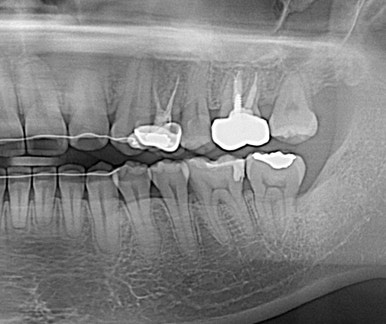

사랑니의 쓸모를 찾아서~

사랑니 교정

사랑니를 교정치료를 통해 어금니로 사용하는 케이스